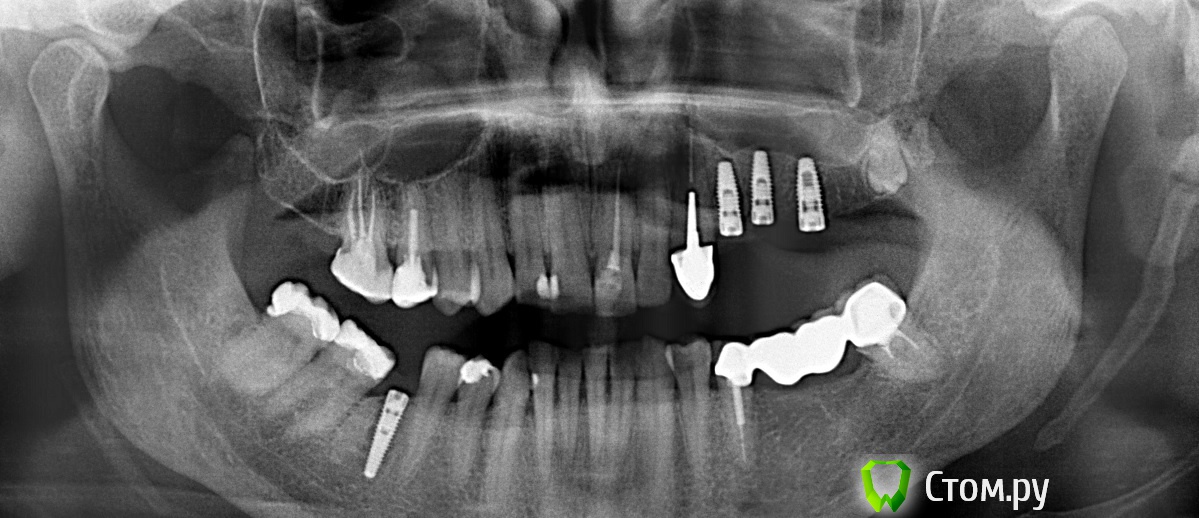

anvladd Опубликовано 2 июня, 2014 Автор Поделиться Опубликовано 2 июня, 2014 доктора что не так с 46? Ссылка на комментарий

zzkz Опубликовано 2 июня, 2014 Поделиться Опубликовано 2 июня, 2014 доктора что не так с 46?там не корень дистальный случаем? Ссылка на комментарий

sydnik Опубликовано 2 июня, 2014 Поделиться Опубликовано 2 июня, 2014 похоже на корень Ссылка на комментарий

anvladd Опубликовано 4 июня, 2014 Автор Поделиться Опубликовано 4 июня, 2014 (изменено) Так что делать то? Завтра снимок выложу.Забыл написать, спозиционировал его в нужном положении и поставил коронку на врем цемент, отправил к хирургу.снимок в день прокручивания импланта 2.5 Изменено 4 июня, 2014 пользователем anvladd Ссылка на комментарий